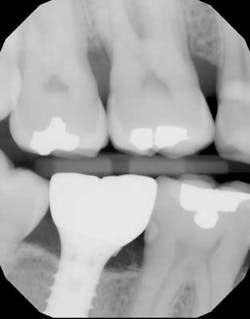

As a periodontist, I am not involved much with this phase. We simply schedule the patient for a “postrestorative check” two to three months after the prerestorative check. During this appointment, final photographs are taken, baseline probing depths are recorded, occlusion is checked, implant hygiene and home care are reviewed, and a final bitewing radiograph is taken to check for residual cement. The patient is also reminded about the importance of proper maintenance to protect their investment.

Radiopaque material noted on mesial of newly restored implant No. 31 during postrestorative check.